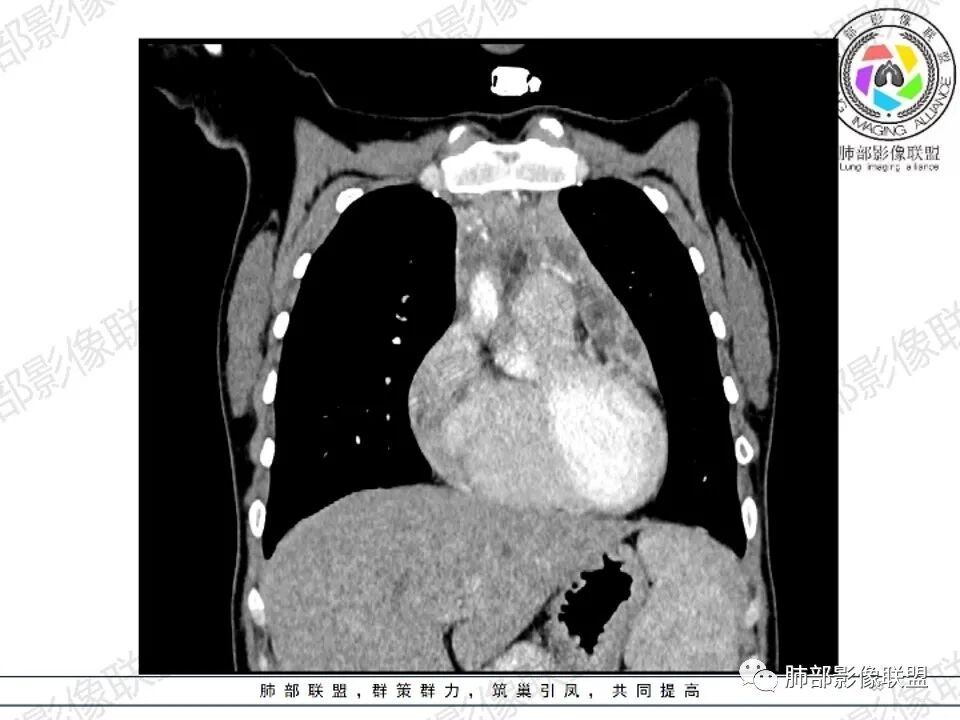

女,27,间断头晕、乏力3年,左眼视物模糊2月。贫血。胸部CT:前纵隔不规则肿块,多结节融合,边界不清,沿主动脉及肺动脉间隙生长,平扫密度欠均匀,增强扫描可见多发低密度坏死,纵隔血管供血穿行,腋窝多发大小不等淋巴结肿大。考虑恶性病变,胸腺癌?肉瘤?淋巴瘤?鉴别胸腺瘤、结节病等。

临床:年轻女性,慢性病程,多系统病变,头晕,贫血,视物模糊。

CT:定位纵膈病变,前中纵隔多发肿块,质软,塑形,密度不均匀,边界清楚。增强不均匀强化,坏死边界清楚,血管漂浮征。双侧腋下多组淋巴结肿大,明显异常强化。

2.影像显示前纵隔不规则块状影,依势贴附心脏大血管旁,密度不均,边界不甚清楚,有结节融合感。

3.病灶轻度不均匀强化,可见血管穿行,散在液性低密度区。

双肺门未见肿大淋巴结。

4.双侧腋窝区见增大淋巴结,边界清楚。

1.年轻女性,前纵隔不规则块状影,密度不均,边界不甚清楚,有结节融合感,轻度不均匀强化,可见血管穿行,最常见最符合的无疑是淋巴瘤!